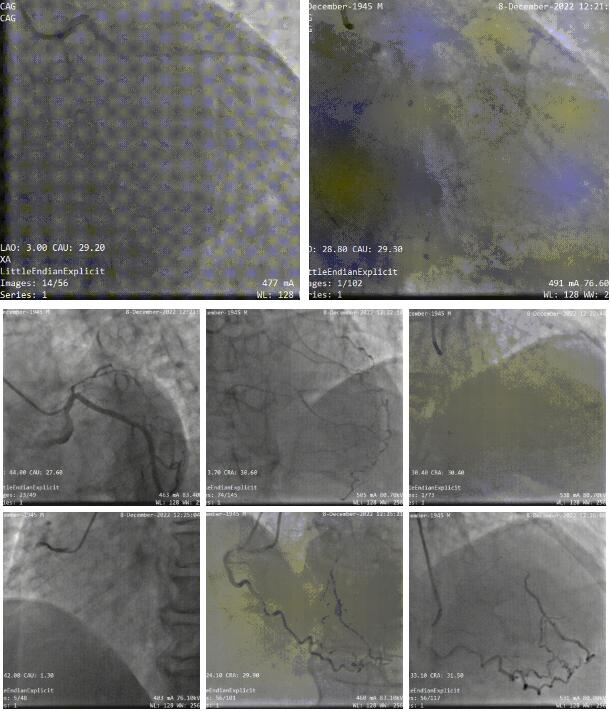

患者是一位77岁的高龄男性,2022.12因为不稳定心绞痛入住我科,查心超提示:左室下壁收缩活动减弱,左房、左室增大,轻度二尖瓣反流,LVEDd 60mm,EF 45%;查NT-proBNP 1771ng/L;冠脉造影提示:冠脉右优,右冠近端第一转折处完全闭塞近端通过锐缘支发出侧枝循环供应前降支;旋支斑块;前降支近端对角支后完全闭塞,远端可见来自右冠及自身侧枝循环;周浩教授团队先行右冠PCI,corsair+XTA通过右冠闭塞段,植入两枚支架。拟择期行前降支PCI。

第一次PCI造影

PCI,corsair+XTA通过右冠闭塞段,植入两枚支架,术后结果。